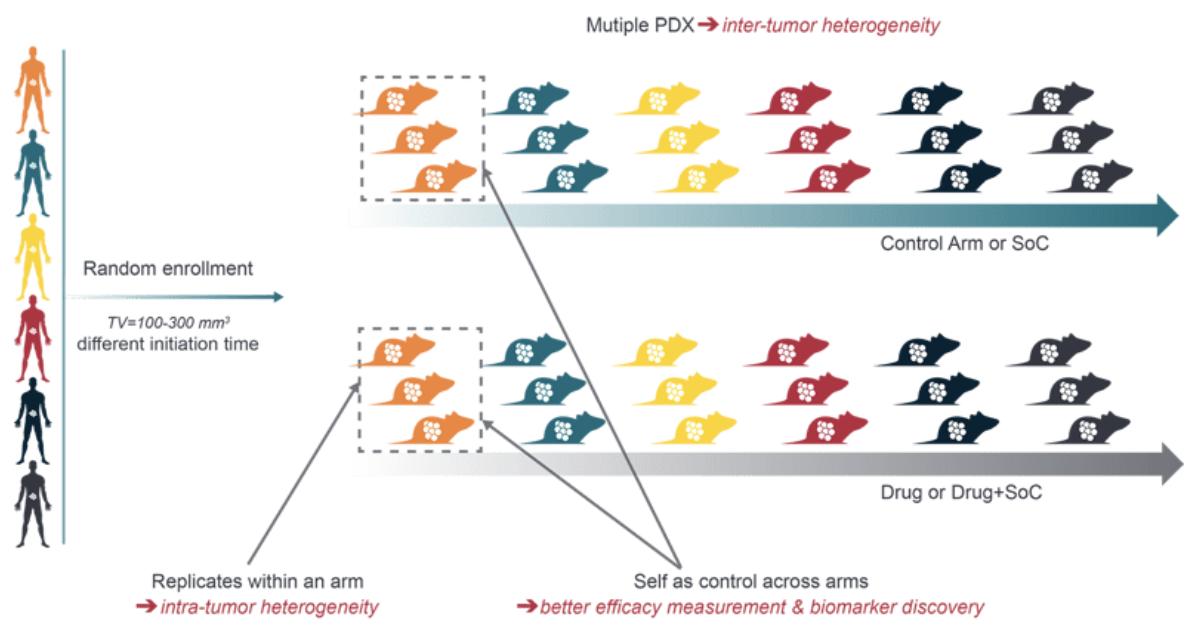

Did you know many oncology therapies fail in Phase II clinical trials due to a lack of efficacy? Crown Bioscience’s PDX Mouse Clinical Trials (MCTs) address this challenge by offering a robust, clinically relevant platform designed to improve the predictability of preclinical studies.

Figure. A representative PDX Mouse Clinical Trial Design

Figure. A representative PDX Mouse Clinical Trial Design

With the world’s largest collection of over 2,600 PDX models, our MCTs help bridge the gap between preclinical and clinical stages, enabling:

With 12+ years of experience and over 300 successful MCT projects, Crown Bioscience is your trusted partner, supporting the journey from preclinical studies to clinical validation with unmatched expertise and resources.